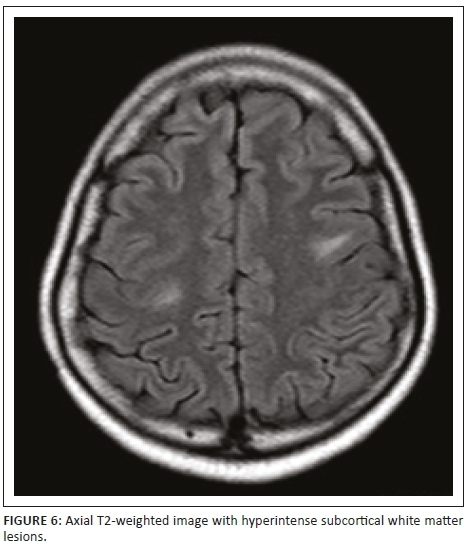

Magnetic resonance imaging of the cervical spine revealed a T2 hyperintense central grey matter lesion extending longitudinally and contiguously across three vertebral body lengths. Brain MRI demonstrated similar T2 hyperintense lesions involving the splenium of the corpus callosum, the midbrain and centrum semiovale. There were no perivenular radially oriented lesions (Dawson fingers) that are typical of MS.

The lesions in NMO are typically hyperintense on T2-weighted images. The distribution is observed in the regions of the central nervous system known to be rich in AQP4, typically in a periependymal distribution in the periventricular white matter, corpus callosum and central grey matter of the spinal cord.5

Both MS and NMO present with circumventricular cerebral lesions; however, there are salient defining imaging features that distinguish these conditions on imaging. MS frequently presents with discrete, ovoid lesions which lie perpendicular to the ventricles (radially oriented perivenular lesions commonly referred to as 'Dawson fingers').5,6 In contradistinction, the lesions in NMO occur along the ependymal lining of the lateral ventricles, the regions around the third ventricle, cerebral aqueduct and fourth ventricle. These are heterogeneous, oedematous and form large confluent lesions creating a 'marbled pattern'. There may be notable involvement of the splenium presenting as a unique 'bridging arch pattern' as was demonstrated in this case (Figure 4).2,5,6 Similar large, confluent and heterogeneous lesions occur in the cerebral white matter, which may be contiguous with the periependymal lesions.